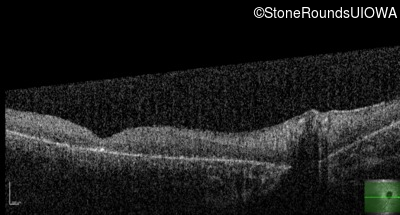

Optical Coherence Tomography - Right - <1/700 sc

Exemplar / OCT Stack